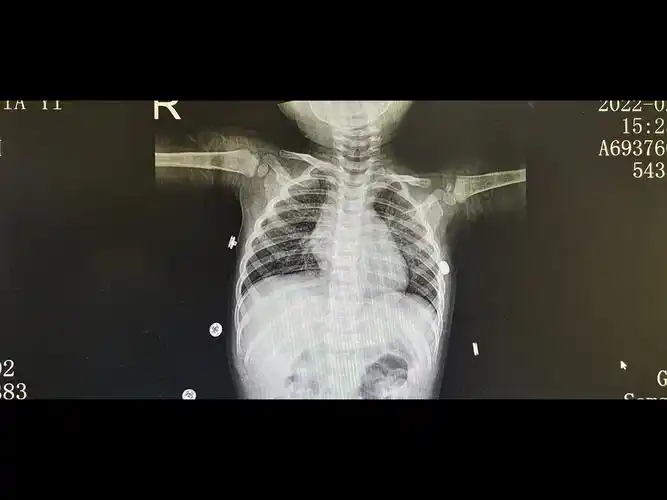

孩子3周岁多点,支气管肺炎入院治疗,6天后,孩子明显好转,医生依然让

中医院放射科带您解读小儿肺炎

女童未及时就医诊断小儿支气管肺炎联合用药得以缓解

小孩四岁发烧不退诊断为肺炎,帮忙看下两次片子是否好了

两岁小孩两个月来反复感冒鼻塞咳引起支气管肺炎住,现在又鼻塞咳嗽